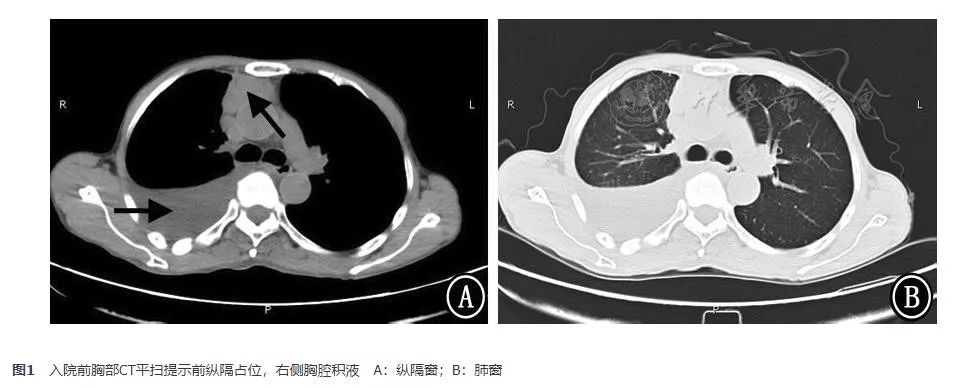

入院后查甲状腺及颈部淋巴结B超未见异常。肺通气灌注显像提示:右肺下叶前基底段、后基底段及左肺上叶尖后段多发通气与血流灌注下降灶(匹配);余双肺通气及血流灌注未见异常,无肺栓塞依据。经过胸腔抽液后,复查肺动脉血管CT造影(2017年11月24日)提示肺血管未见明显异常,前纵隔占位(增强后CT值增加28 HU左右);两肺下叶炎症、右侧胸腔积液,较前片(2017年11月15日)好转;两肺多发纤维灶,右肺上叶微小结节(图2)。

图2 肺动脉血管CT造影 A、B:前纵隔占位(箭头示),增强后CT值增加28 HU左右;C、D:右侧包裹性胸腔积液(箭头示)